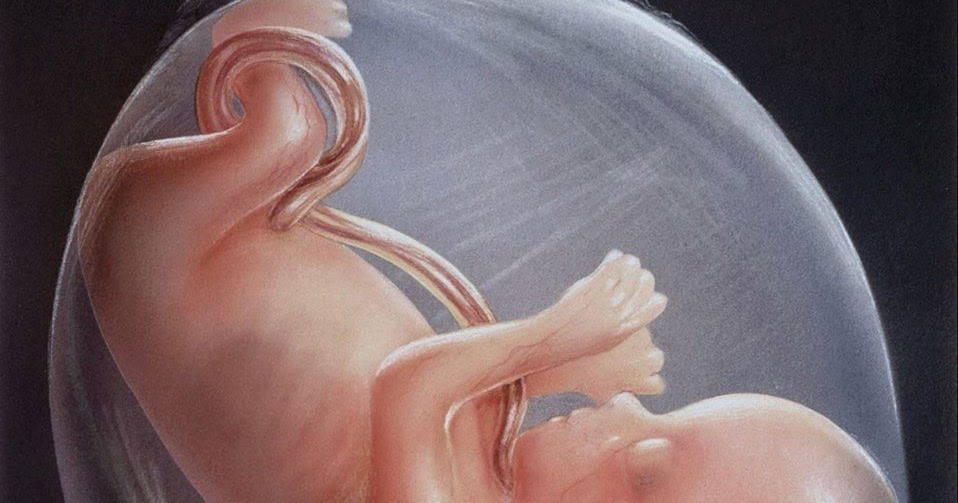

Медицинские аспекты мекония в околоплодных водах